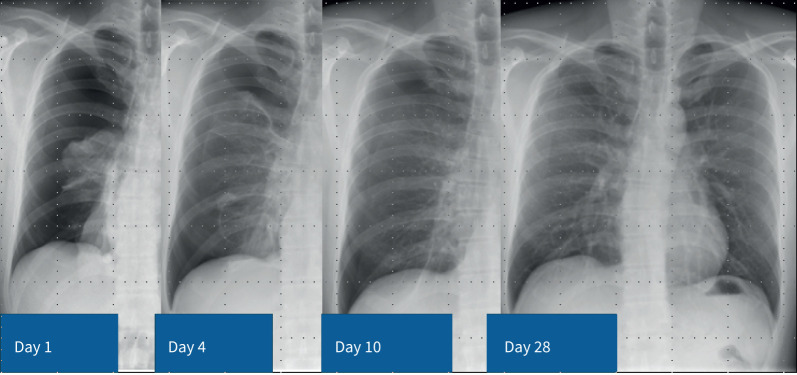

气胸是由肺部气体泄漏到胸膜间隙引起的。如果漏气已经愈合,气胸可能不需要干预,但需要时间来解决。尽管解决了空气泄漏,但根据患者的偏好,程序性管理可能是有保证的。持续的空气泄漏有张力性气胸的风险,需要干预。对于再次发作的气胸或患者因素(如职业风险),应考虑手术预防复发性气胸。这篇综述的目的是描述最近气胸治疗模式向个性化管理转变的证据基础,新指南的支持,以及新型诊断/管理辅助工具(如胸部超声和数字引流系统)的应用。

Pneumothorax arises from pulmonary air leaking into the pleural space. If the air leak has healed, the pneumothorax may not require intervention but will take time to resolve. Procedural management may be warranted, despite resolution of the air leak, depending on patient preference. An ongoing air leak carries a risk of tension pneumothorax and requires intervention. Surgical prevention of recurrent pneumothorax should be considered in cases with a second episode or for patient factors (e.g. occupational risk). This review aims to describe the evidence base for the recent paradigm shift towards individualised management in the treatment of pneumothorax, supported by new guidelines, and the utility of novel diagnostic/management adjuncts such as thoracic ultrasound and digital drainage systems.